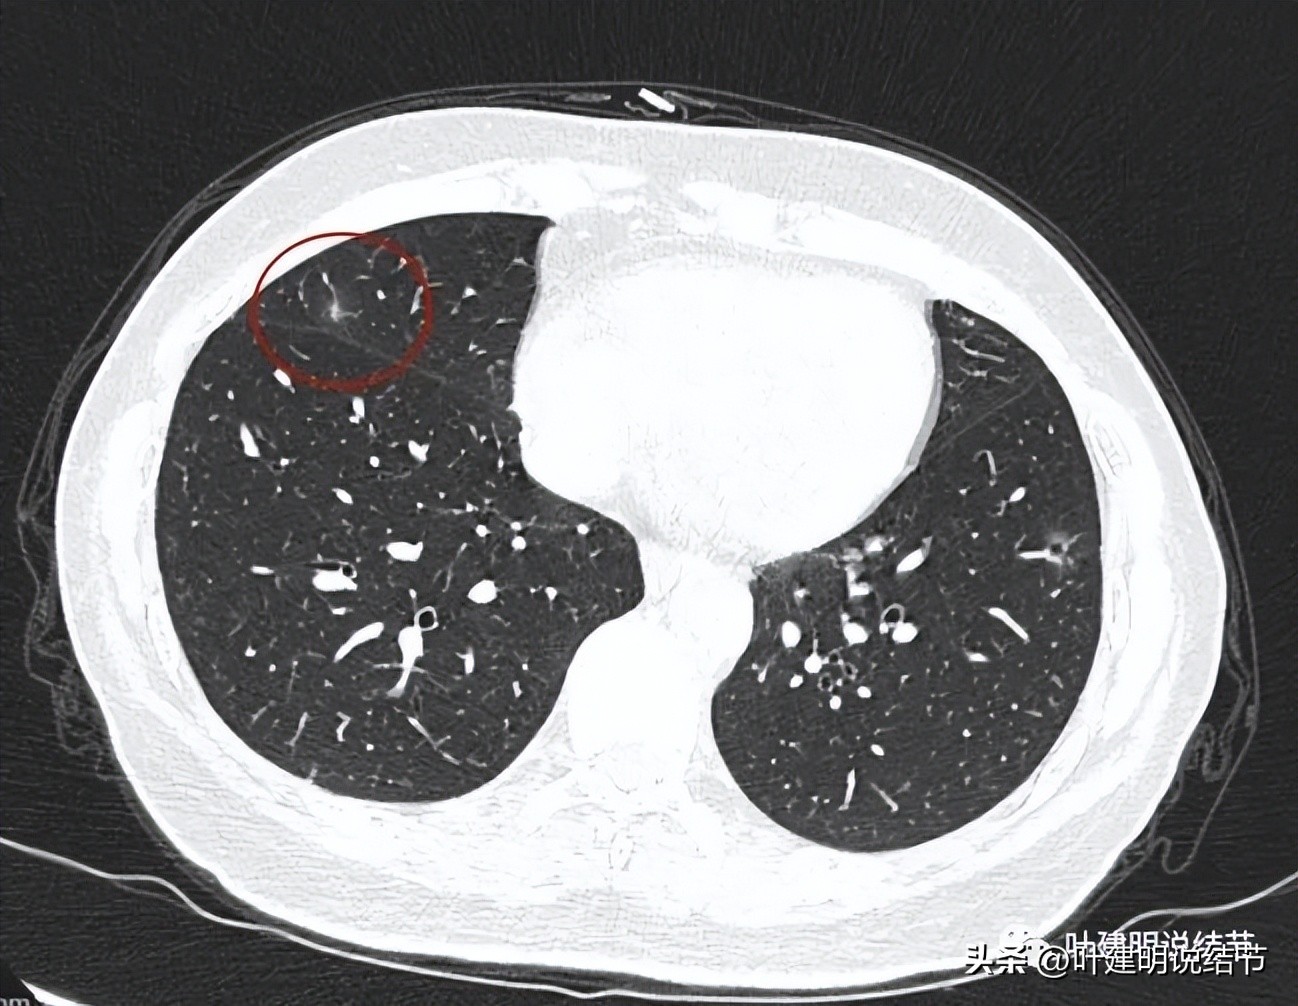

再看左下叶的主病灶,此层见其是磨玻璃密度,轮廓较清,内部密度欠均匀。

有明显血管征,血管进入后有分支发出,病灶表面显得有毛刺样。

病灶中间有空腔。

囊壁较薄,但不均匀,有的地方还是显略厚了点的。

似乎见微小血管走向病灶。

微小血管征确实有。

靶重建后发现病灶囊腔型,桔色箭头示进入的血管有异常增粗,而且壁显得毛糙;黄色箭头示空腔;红色箭头示整体轮廓较清;绿色箭头示有磨玻璃成分,虽然密度较低;蓝色箭头示病灶略有胸膜牵拉影响,只是力较弱而已。

上图显示了病灶轮廓与瘤肺边界其实还是清楚的。

部分边缘有毛刺征可见。

显示明显的血管征与血管异常增粗和壁毛糙。

上图显示病灶轮廓较清,有锐利细毛刺征,灶内有弯曲血管穿行。

囊壁有少许是偏实性成分的,如粉色箭头所示。

血管增粗进入并散开来。

血管在病灶内发出分支。